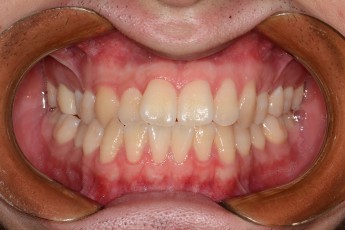

BEFORE & AFTER

- 돌출입교정